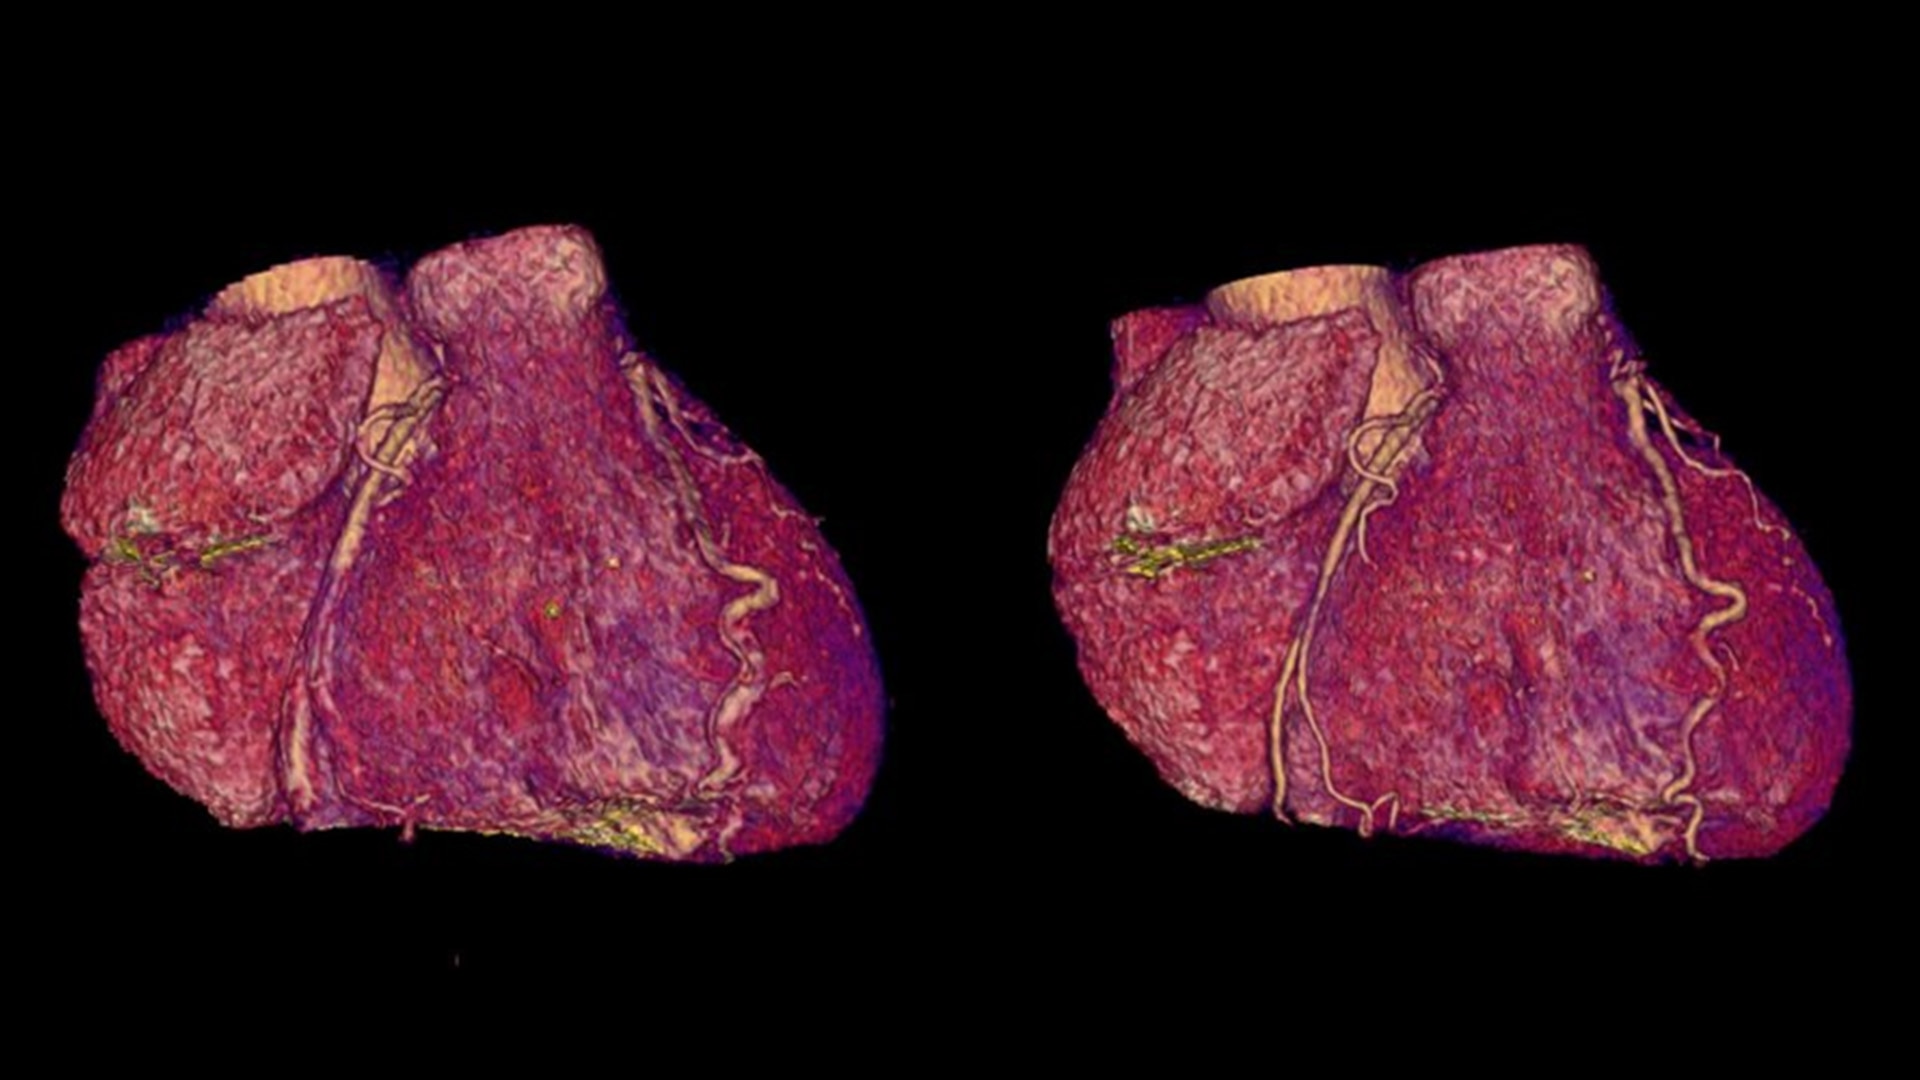

SnapShot Freeze 2

Intelligent and automated whole-heart motion correction for enhanced Cardiac CT imaging.

Motion correction

6x reduction in motion artifacts1